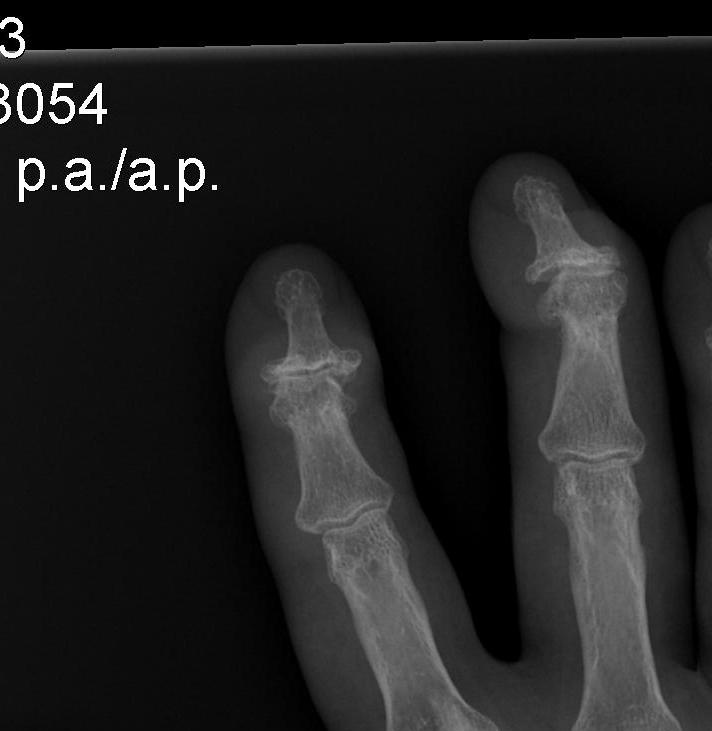

Affected joints

Base thumb

PIPJ / Bouchard's nodes

DIPJ / Heberden's nodes

Xray

Joint space narrowing

Subchondral sclerosis

Osteophyte formation